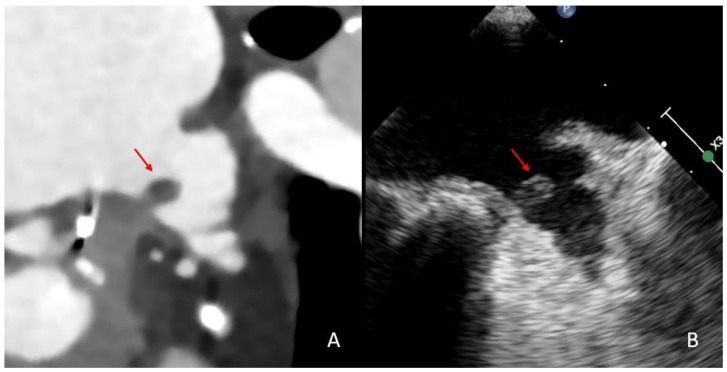

Background: Large vessel occlusion (LVO) strokes account for a significant proportion of ischemic strokes and are often cardioembolic in origin, particularly following atrial fibrillation (AF) with thrombus formation in the left atrial appendage (LAA). Although direct oral anticoagulation (DOAC) therapy reduces stroke risk in AF, anatomical and flow-related factors may still allow thrombi to form and persist, revealing the limitations of anticoagulation in high-risk patients. Examining structural and hemodynamic factors contributing to thrombus persistence is essential for optimizing patient management. Methods: We retrospectively analyzed 169 AF patients with LVO stroke who underwent cardiac CT (cCT) during acute stroke assessment. Patients were categorized based on the presence or absence of persistent LAA thrombi and further stratified by DOAC status. LAA volume, blood stasis and left ventricular (LV) diameter were measured. Thrombi were assessed using Hounsfield Unit (HU) analysis to evaluate potential differences in thrombus composition. Logistic regression analysis was performed to identify independent predictors of thrombus persistence with adjustment for DOAC therapy. Results: Persistent LAA thrombi were identified in 23 patients (13.6%). Patients with thrombi had significantly higher rates of stasis (p = 0.004), larger left ventricular diameters (p = 0.0019) and higher LAA volumes (p = 0.004). When adjusted for DOAC therapy, larger LAA volume (OR 1.05, p = 0.011), presence of LAA stasis (OR 6.14, p = 0.013) and increased LV diameter (OR 1.06, p = 0.006) were independent predictors of thrombus persistence. Thrombus size and HU values did not differ significantly between DOAC and non-DOAC groups. Notably, 30.4% of patients with persistent thrombi were on adequate DOAC therapy. Conclusions: LAA volume, stasis and LV enlargement predict thrombus persistence in the LAA of AF patients with LVO stroke, even under adequate DOAC therapy. These findings highlight the potential need for alternative antithrombotic strategies, including interventional LAA occlusion, and warrant further investigation into individualized stroke prevention in high-risk AF populations.